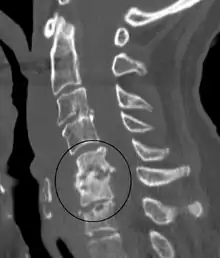

| Discitis in a 2 year old child. | |